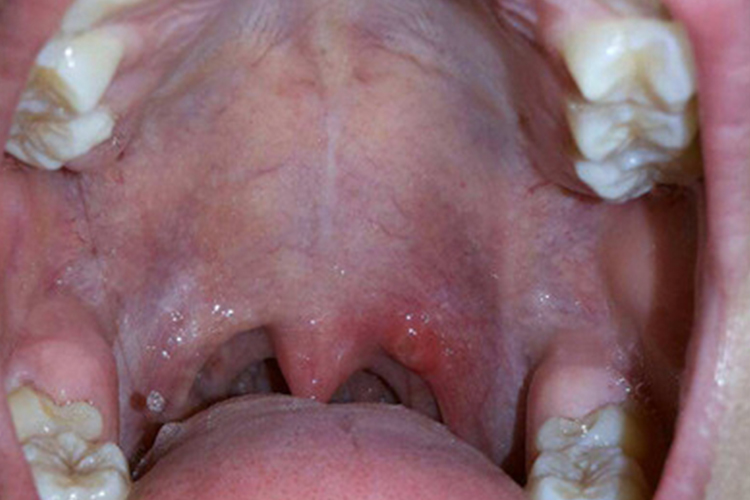

艾滋病初期咽喉炎患者进行咽喉检查时,可见咽部充血、红肿、水肿,同时咽喉伴随有干痒、灼热、疼痛、异物感以及咳嗽、咳痰等,甚至可出现呼吸困难的症状。